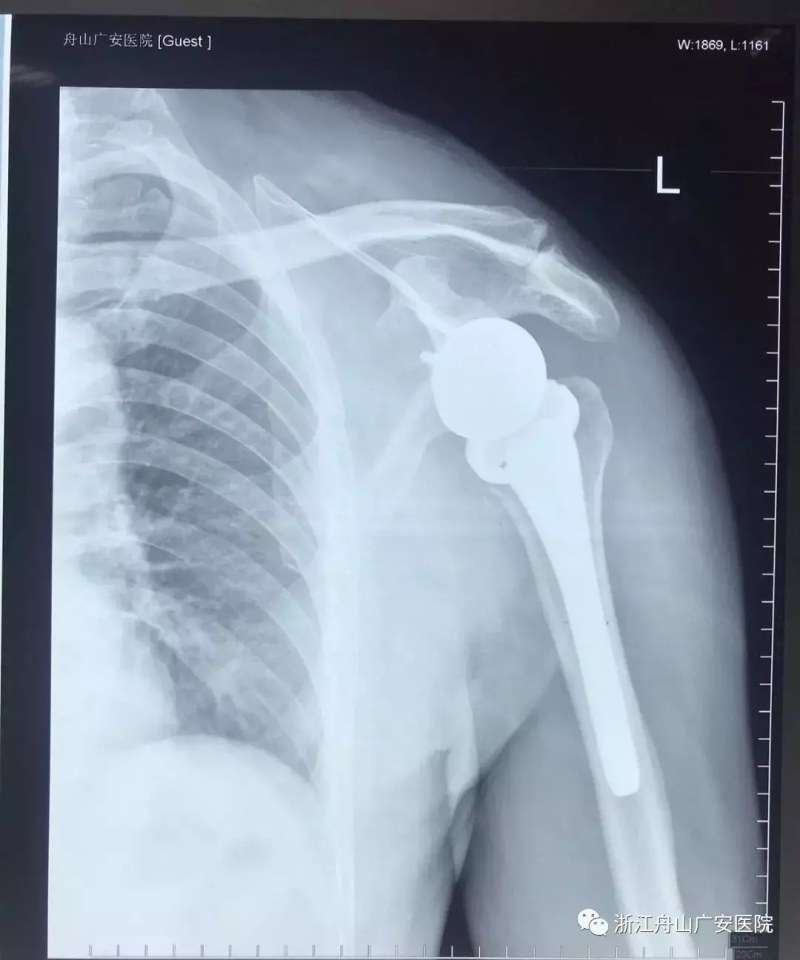

反式肩關(guān)節(jié)置換術(shù)后照片

反式肩關(guān)節(jié)置換術(shù)在國際上都屬于先進(jìn)的技術(shù),此項(xiàng)技術(shù)多應(yīng)用于老年患者的肱骨近端4部分骨折;合并明顯肩袖損傷的肱骨近端粉碎性骨折;肩袖撕裂伴有關(guān)節(jié)炎病;大肩袖撕裂伴有假癱;不可修復(fù)的肩袖撕裂;失敗的初次肩關(guān)節(jié)置換;肱骨近端骨折內(nèi)固定失?。魂惻f性固定性肩脫位、肱骨近端腫瘤等。反肩關(guān)節(jié)置換(還有如反式肩關(guān)節(jié)、反肩、反球肩關(guān)節(jié)等叫法)隨著假體設(shè)計(jì)的不斷改進(jìn)和肩關(guān)節(jié)手術(shù)技術(shù)的不斷提高,成為肩關(guān)節(jié)醫(yī)師的“壓軸”法寶。這類假體的“頭在上、盂在下”和我們真正的肩關(guān)節(jié)方向相反。通過這樣的設(shè)計(jì),關(guān)節(jié)的旋轉(zhuǎn)中心下移并內(nèi)移,凹關(guān)節(jié)面支撐,凸關(guān)節(jié)面負(fù)重,使得三角肌能夠直接發(fā)揮帶動(dòng)肩關(guān)節(jié)活動(dòng)的作用。應(yīng)用這種假體可以幫助我們克服上述難題,為上述身處煎熬的患者帶來福音,成就患者精妙的肩關(guān)節(jié)“錦軸”。